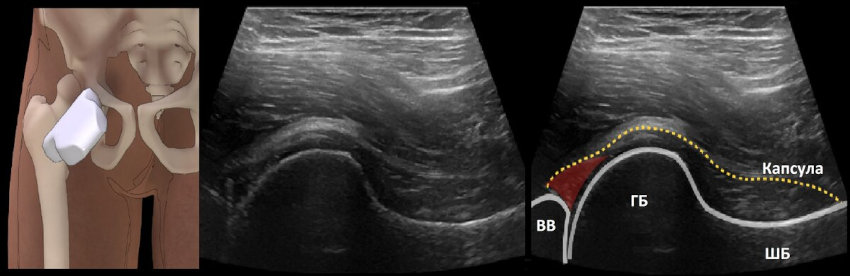

Остеоартроз тазобедренных суставов - это хроническое заболевание, при котором происходит полное или частичное разрушение хрящевой ткани, поражаются мышцы, связки, костная ткань .

Остеоартроз тазобедренных суставов сопровождается постепенным разрушением хрящевой ткани и деформацией сочленения . Существует 3 степени болезни .

Остеортроз тазобедренного сустава Коксартроз или остеоартроз тазобедренного сустава - заболевание, относящееся к дегенеративно-дистрофическим . Коксартрозом преимущественно болеют люди среднего и пожилого . . .